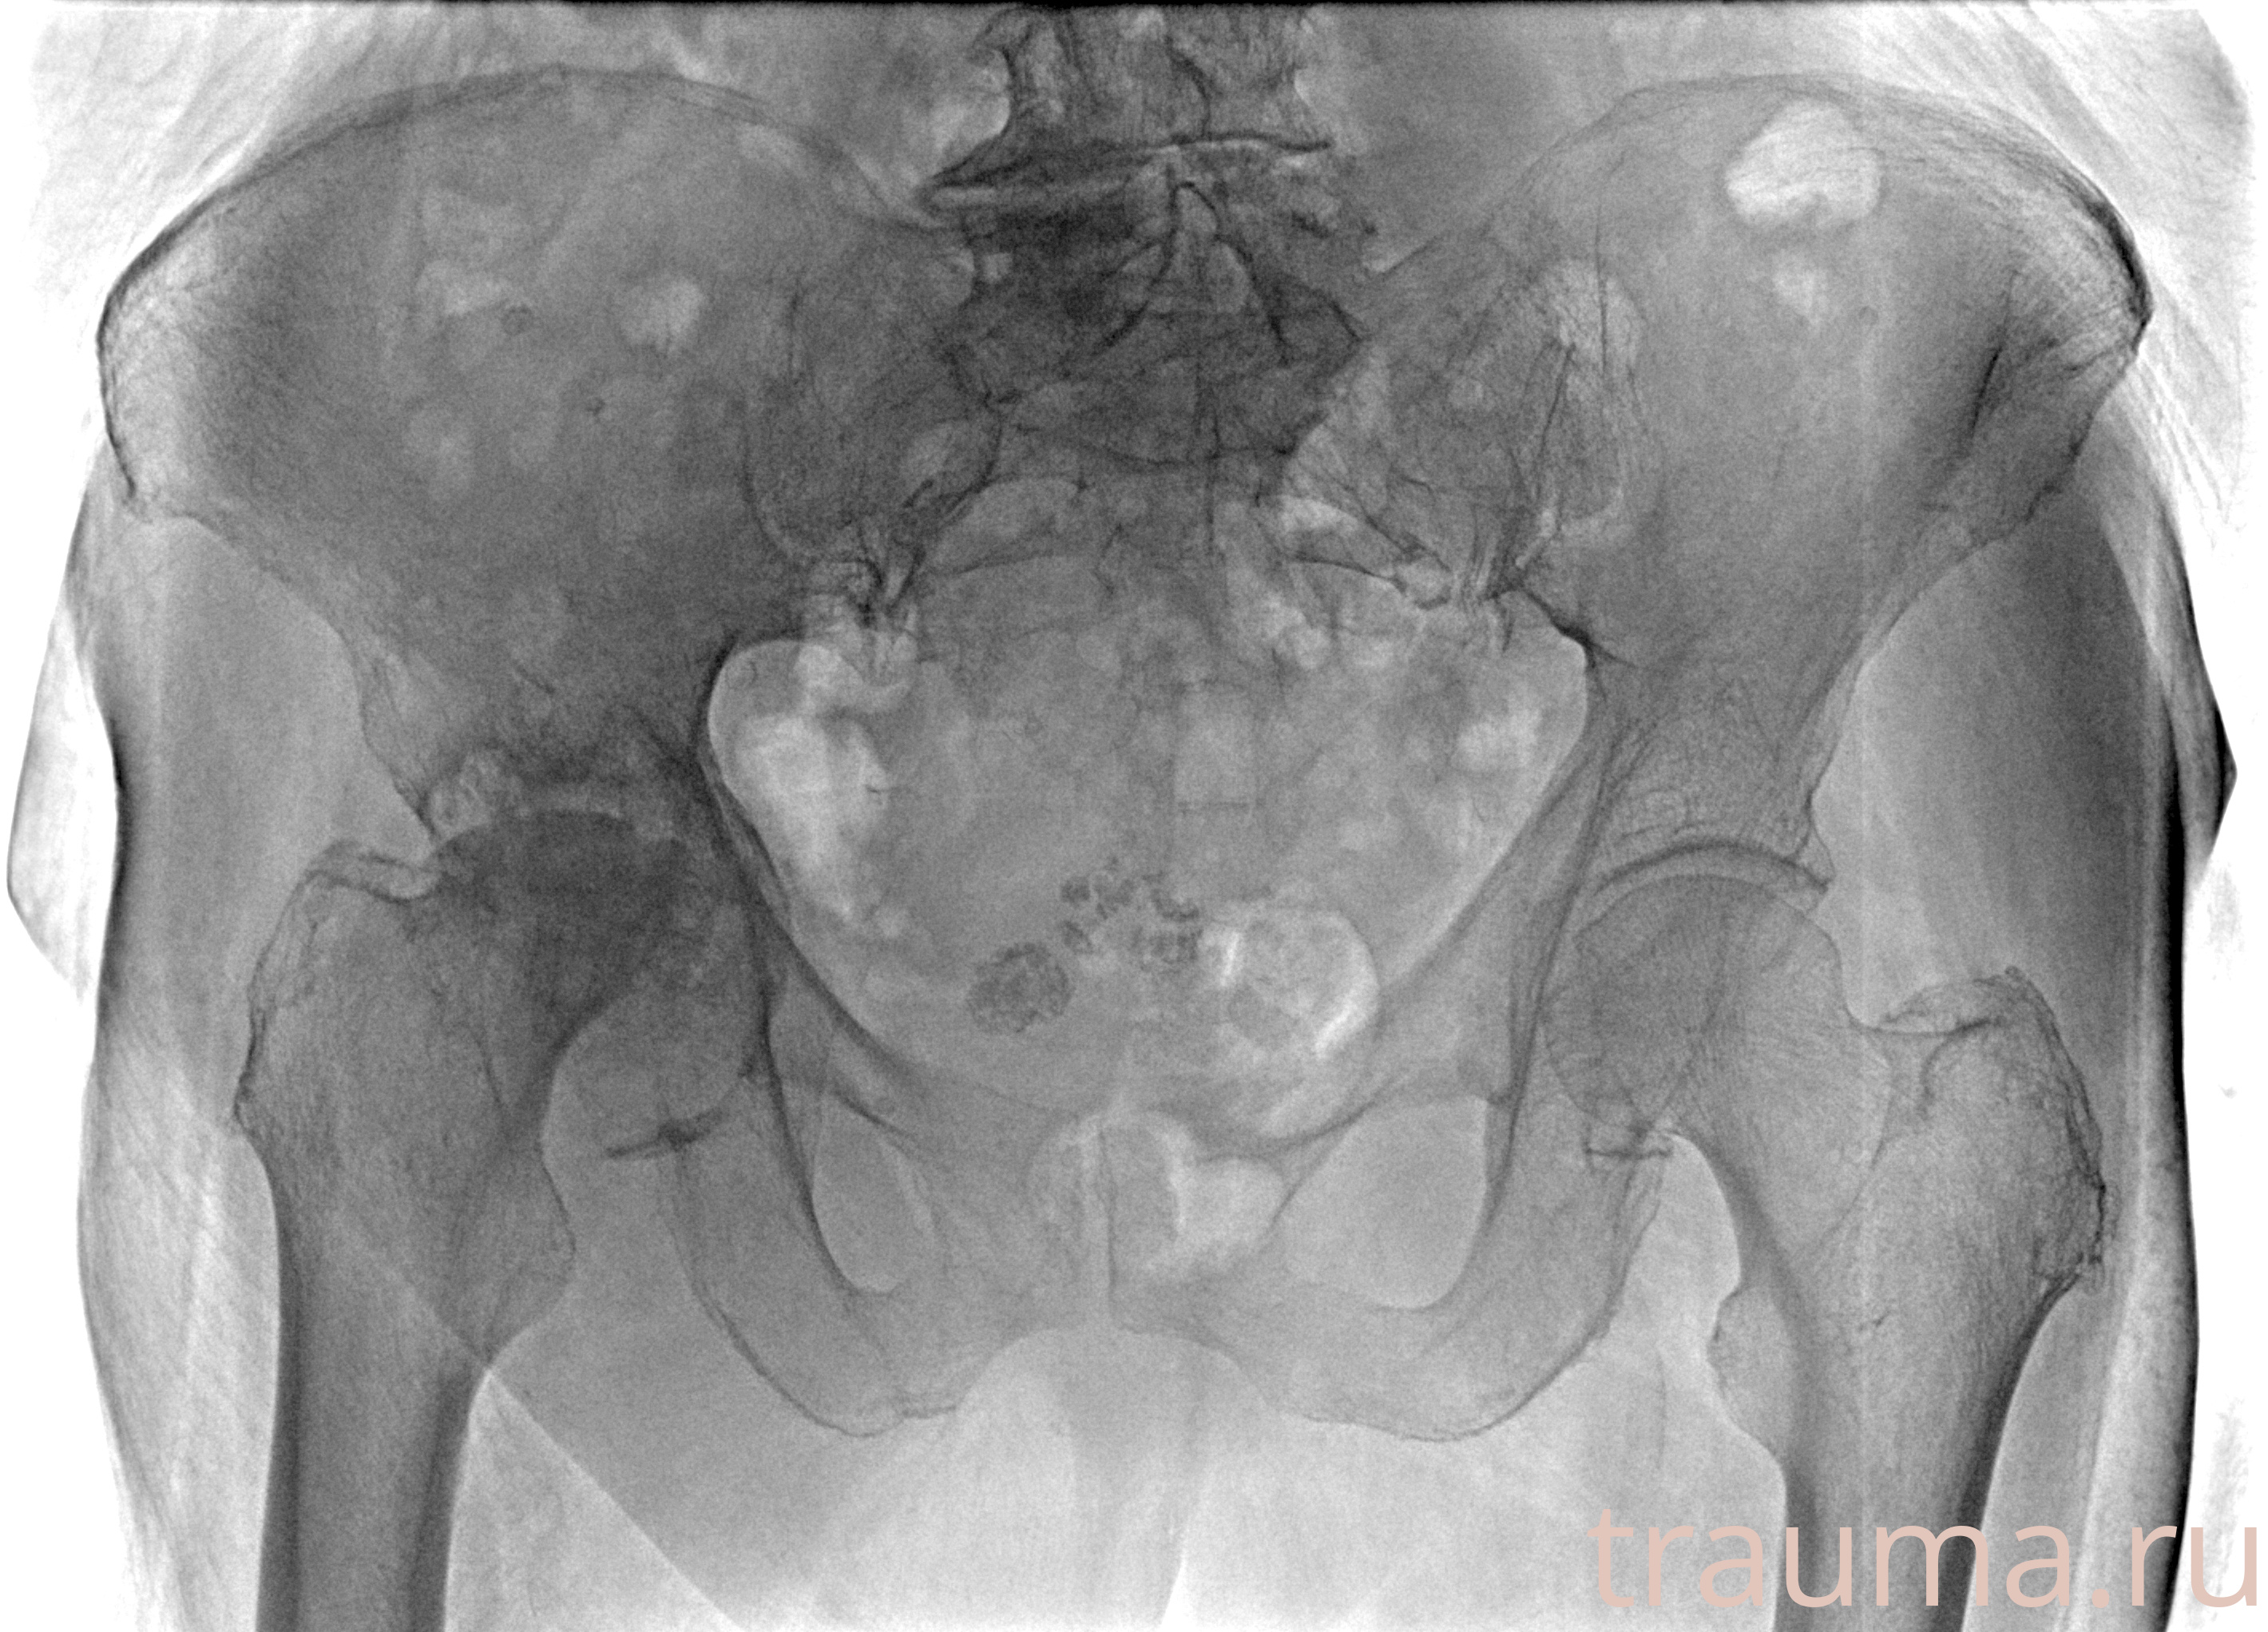

Рентген на дому: по вашему адресу приезжает врач-рентгенолог, травматолог-ортопед с мобильным рентгеновским аппаратом, проводит диагностику травмы или заболевания, делает необходимые рентгенограммы, дает рекомендации по дальнейшему лечению. Получить качественные снимки в домашних условиях возможно благодаря уникальной методике, разработанной МосРентген Центром для института  Склифосовского